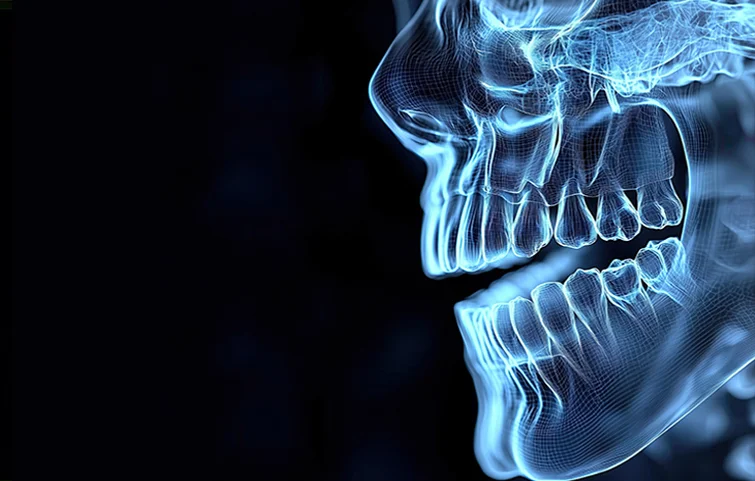

Jaw fractures are breaks in the jawbone, commonly affecting the mandible (lower jaw) or the maxilla (upper jaw). They can result from trauma, such as falls, sports injuries, or accidents, and can lead to significant functional and aesthetic issues if not properly treated.

Jaw fractures, particularly of the mandible or maxilla, are commonly caused by trauma from accidents, sports injuries, or violence. Diagnosis begins with a thorough clinical evaluation. The patient may present with facial swelling, bruising, pain, difficulty in opening or closing the mouth, malocclusion (improper bite), and numbness due to nerve involvement.

Physical examination includes assessing jaw alignment, mobility, and palpation for stepoffs or crepitus. Intraoral examination checks for bleeding, lacerations, or tooth mobility. Imaging is crucial for confirmation. A panoramic X-ray (orthopantomogram) is a common initial tool to visualize the mandible. However, computed tomography (CT) scans are the gold standard for complex fractures or midface injuries, providing detailed 3D visualization of bone involvement.

In some cases, cone-beam CT (CBCT) may be used, especially in dental settings, to assess smaller or localized fractures. If the fracture involves the condyle or temporomandibular joint, additional TMJ-specific views may be needed. Associated injuries such as dental fractures or airway compromise should also be evaluated.

Treatment decisions are guided by imaging findings, location of the fracture (e.g., angle, symphysis, condyle), displacement, and patient symptoms. The goal of diagnosis is not only to confirm the fracture but also to assess complications, such as infection, nerve damage, or airway obstruction, ensuring timely and appropriate surgical or non-surgical intervention.